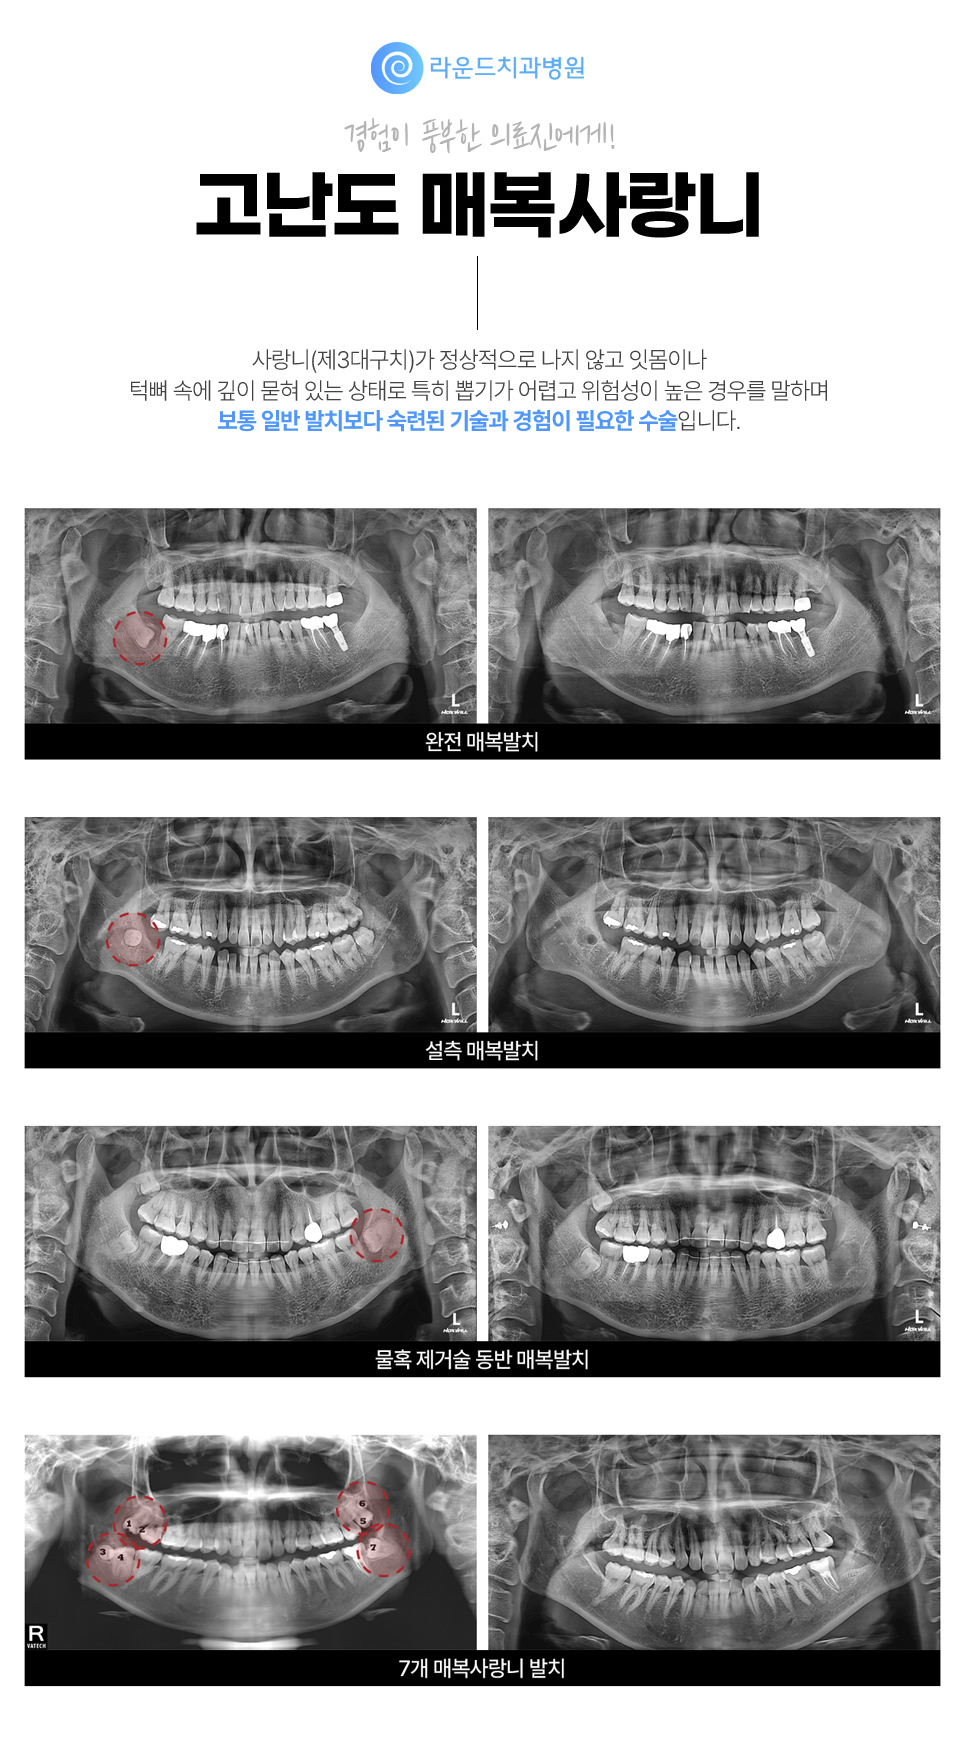

• 고난도 매복사랑니